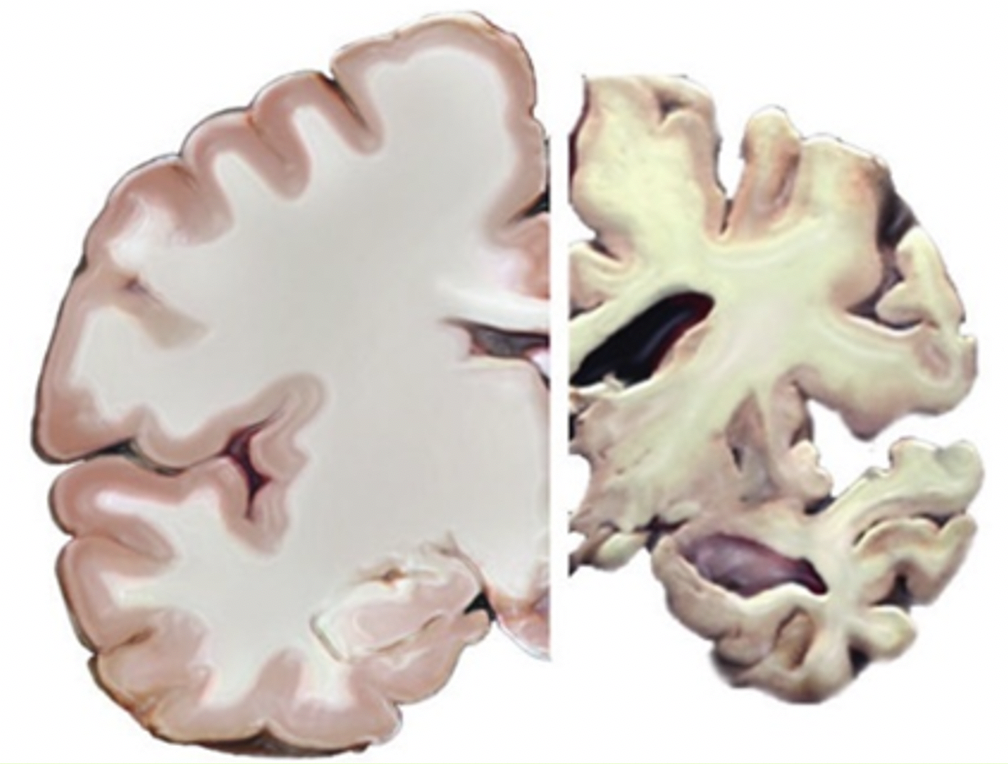

到底是什么导致了大脑患上这种病,其实目前还不清楚。但我们能观察到,大脑在患病后会慢慢萎缩。

这两个问题的复杂程度,我大概用几十万字都没法说清楚。简而言之,是大脑中的神经细胞发生了变化。在显微镜下观察大脑切片,你会看到很多长得像树一样的细胞,叫做神经细胞。正常情况下,这些神经细胞之间是相连的,而相连的地方叫突触,而突触是生成记忆的关键。但如果观察阿尔茨海默症患者的大脑,就会发现突触消失了,而且神经细胞里和细胞外会有一些正常大脑中没有的东西,叫做β-淀粉样蛋白。为什么这些东西会出现?要怎么预防和消除它们?目前,这些问题都还没有确切答案,而这就是脑科学家们正在攻克的。